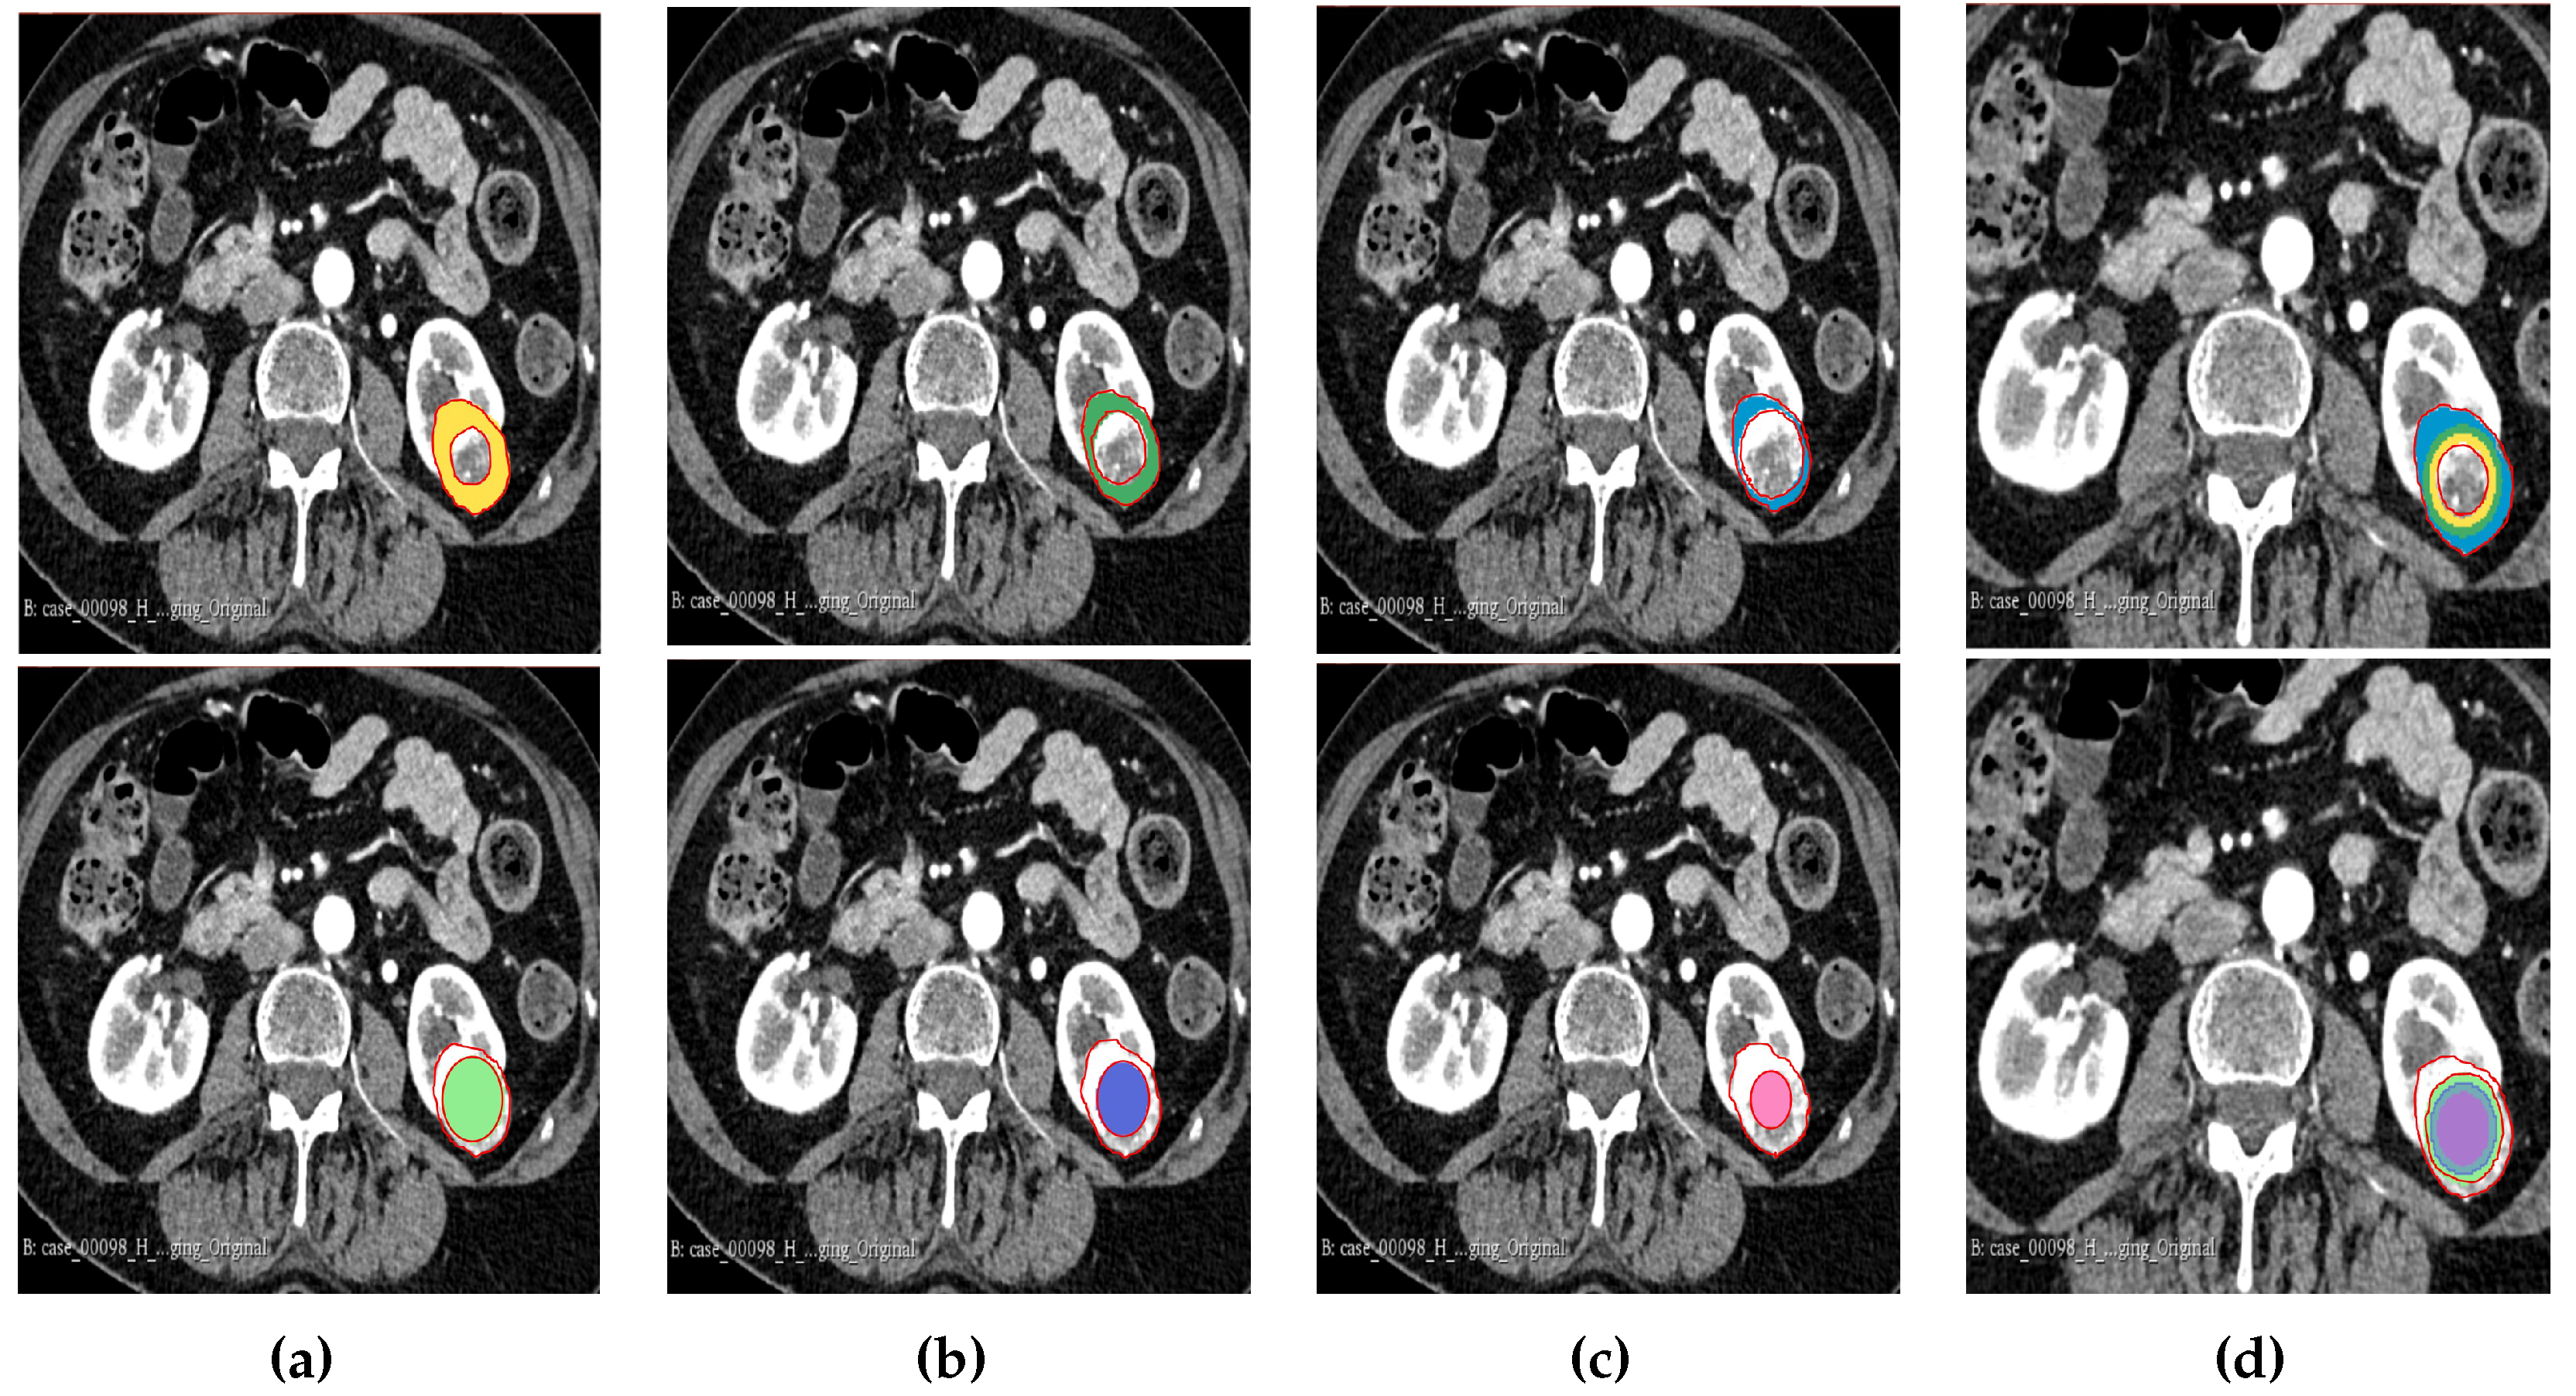

Figure 3. Manual segmentation of the 3D image slices using Slicer 3D software. (a) 75% periphery and core of the tumour. (b) 50% periphery and core of the tumour. (c) 25% periphery and core of the tumour. (d) Overlap of periphery and core subregions.

Figure 4. Representation of the 3D segmented regions. (a) 75% periphery and core of the tumour. (b) 50% periphery and core of the tumour. (c) 25% periphery and core of the tumour. (d) Overlap of periphery and core subregions.